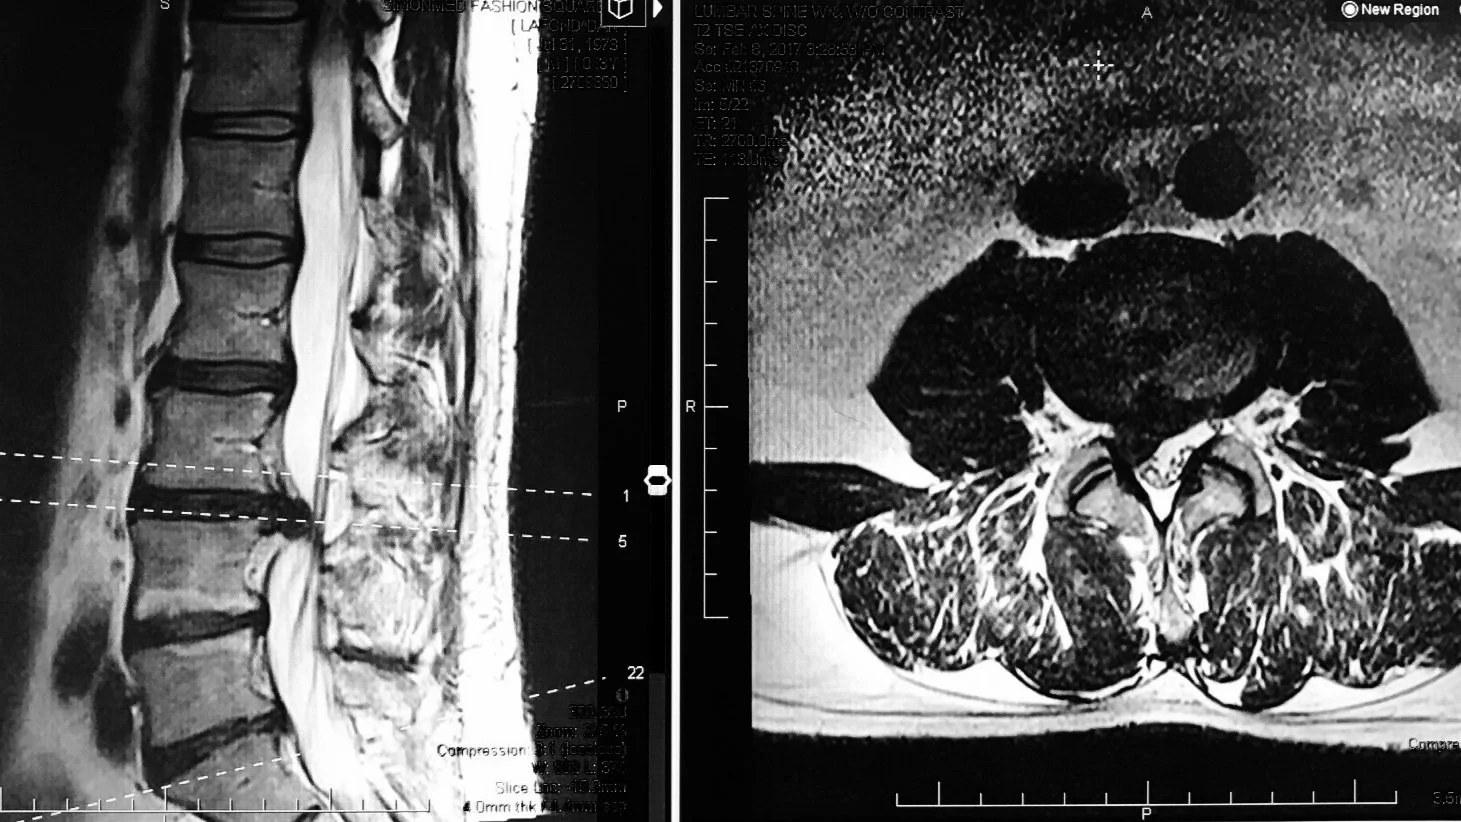

Dr. Gollogly is the only surgeon in the region performing endoscopic spine surgery—the most minimally invasive surgical option available for herniated discs and spinal stenosis. He was also the first surgeon on the West Coast to perform over 1,000 of these procedures, combining technical precision with outpatient efficiency and rapid recovery protocols.

For the last 10 years Dr. Gollogly has been focused on outpatient, minimally invasive spine surgery with an emphasis on endoscopic and microscopic spine surgery in the lumbar spine and cervical disc replacement. As one of the most experienced endoscopic spine surgeons on the west coast, completing his 1,000th case in 2024, he has a very active practice providing patients with procedures with minimal blood loss, short recovery times, and effective solutions for herniated discs, spinal stenosis, and sciatica.

Lumbar Spine